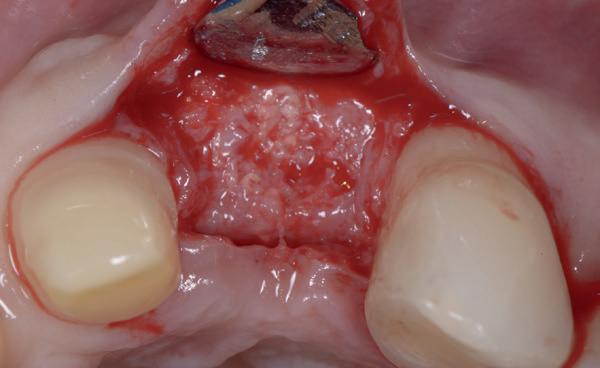

Afbeelding 1 en 2. Een immediate placement (afbeelding 1) is maar weinig invasief en zal weinig nalast geven. Bij een uitgebreide botopbouw (afbeelding 2) daarentegen is de wond veel groter en kan er meer nalast verwacht worden.

In deze casus is extractie van de 37 geïndiceerd in verband met een fistel en restpockets, zoals zichtbaar op de röntgenfoto’s (afbeelding 1). Duidelijk te zien is de forse peri-apicale ontsteking en het botverlies bij de 37, dat zowel richting buccaal als linguaal doorloopt. De 37 wordt atraumatisch verwijderd. Er is aan de linguale zijde veel bot verloren en er is sprake van een perforatie aan de buccale zijde.

Er wordt besloten om botmateriaal te plaatsen in de extractie-alveole. Vervolgens wordt het afgesloten met een titanium versterkt d-PTFE membraan (afbeelding 2). Na vier weken wordt het membraan verwijderd.

Zes maanden na extractie wordt het implantaat 37 geplaatst. Er is sprake van een goede genezing en de processushoogte en -breedte zijn behouden en opgebouwd. Ook is er zichtbaar gekeratiniseerd weefsel

gewonnen. De wond kan na het plaatsen van een healing abutment primair gesloten worden (Afbeelding 3a-3d).